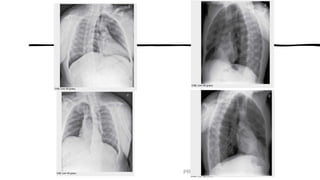

POSICIONAMENTOS DE ROTINA ESPECIAIS

PARA TÓRAX

• AP em decúbito dorsal ou reclinado (semiereta)

• Decúbito lateral

• Apicolordótica

• Oblíqua anterior e posterior

FATORES TÉCNICOS:

• DFR mínima − 183 cm (se possível)

• Tamanho do RI – 35 × 43 cm (14 × 17

polegadas),

longitudinal

• Grade

• Sistemas analógicos ou digitais –

faixa de 100 a 125 kV

• Identificar (D.D ou Semiereto) e

RI

identificando o lado Direito.

Indicações Clínicas

•Esta incidência irá mostrar lesões envolvendo

os pulmões, o diafragma e o mediastino.

AP EM D.DORSAL ou

RECLINADO (semiereto)